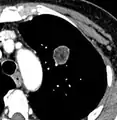

- Enhancement: If the exam is done as a combined non-contrast and contrast CT, a solitary nodule with an enhancement off less than 15 Hounsfield units (HU), whereas a higher enhancement indicates a malignant tumor (with a sensitivity estimated at 98%).[12]

- Areas of fatty tissue (−40 to −120 HU) indicates a hamartoma. However, only about 50% of hamartomas are fat containing.[9]

CT densitometry, measuring absolute attenuation on the Hounsfield scale, has low sensitivity and specificity and is not routinely employed, apart from helping to distinguish solid from ground glass lesions, and to confirm visible fatty areas or calcifications.[12]